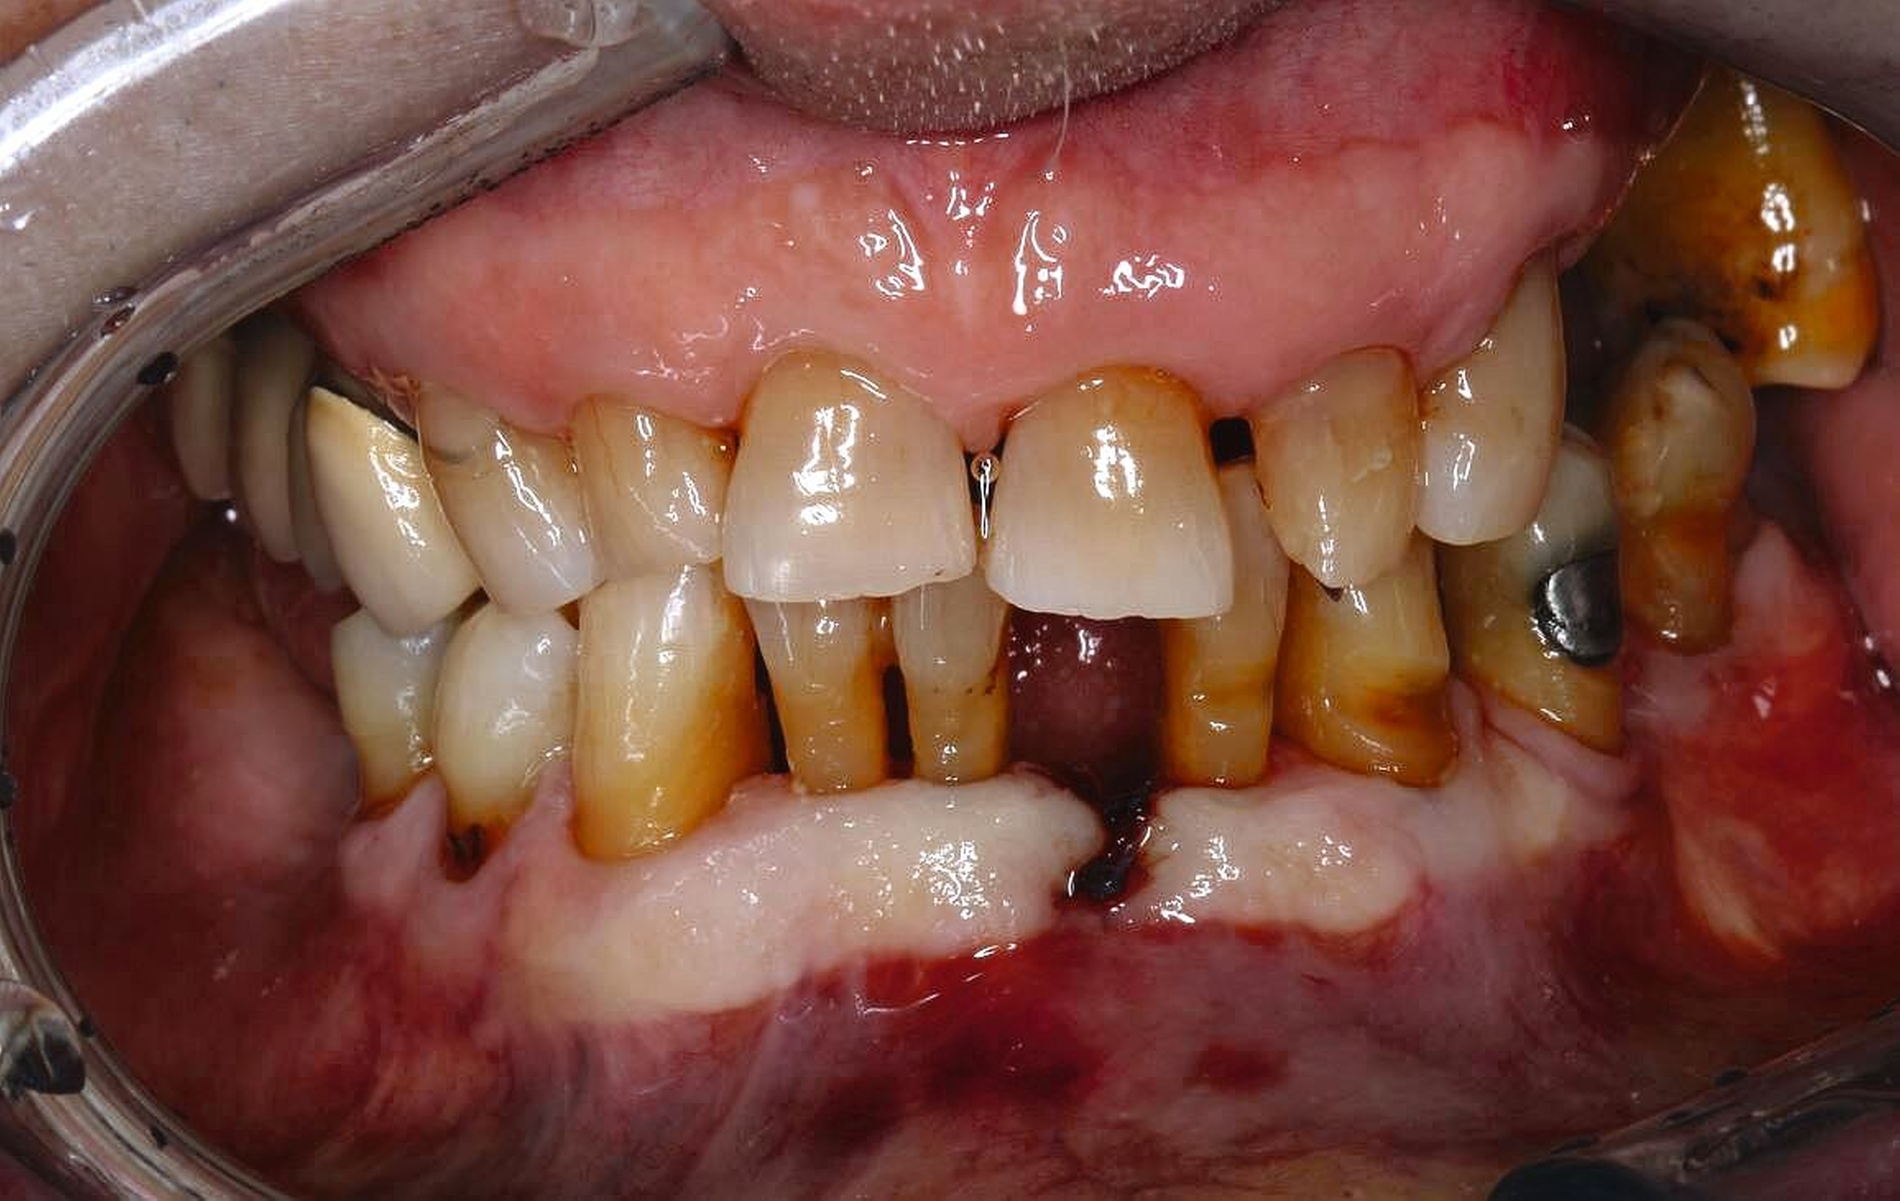

Zahnmedizinische Leitlinien zur zahnmedizinischen Betreuung von geriatrischen und demenziell erkrankten PatientInnen sind aktuell im Entstehungsprozess. Zusätzlich zu den oft komplexen zahnmedizinischen Befunden müssen bei der individuellen Therapieplanung dieser vulnerablen Klientel die Therapiefähigkeit und die Eigenverantwortlichkeit berücksichtigt werden. Dabei ist es weniger das Alter, sondern vielmehr der Zustand der körperlichen und mentalen Funktionsfähigkeit, der den Erfolg zahnmedizinischer Therapien limitiert. Therapien, die bei gesunden Personen jahrelang das Alltagsgeschäft der Zahnmedizin waren, sind bei Personen mit erhöhtem Pflege- und/oder Unterstützungsbedarf eventuell nicht umsetzbar. Gebrechlichkeit (Frailty) ist ein Zustand zwischen guter Gesundheit und Pflegebedürftigkeit im Alter – ein Zwischenstadium, in dem ein vorher fitter älterer Mensch Symptome der Gebrechlichkeit entwickelt und die Gefahr besteht, dass sich sein Zustand verschlechtert. Die geriatrischen Erkrankungen Frailty und auch Demenz sind im Rahmen zahnmedizinischer Behandlungen mit einer reduzierten Kooperations- und Therapiefähigkeit sowie bei der Anfertigung von Zahnersatz mit einer reduzierten Adaptationsfähigkeit assoziiert (Abbildung 3).

Patientinnen und Patienten mit stark reduzierter Therapiefähigkeit profitieren in besonderem Maß von zeiteffektiven Methoden und Materialien, zum Beispiel Bulk-fill-Kompositen, Reparaturfüllungen, Glasionomerzementen oder Intraoralscans. Die Therapiefähigkeit kann – ähnlich wie in der Kinderzahnmedizin – durch ein vertrauensvolles Verhältnis optimiert werden. Anders als in der Kinderzahnmedizin gibt es in der Alterszahnmedizin aber keine altersassoziierten Kontraindikationen für zahnmedizinische Interventionen. Voraussagbare Therapieergebnisse sind von besonderer Bedeutung, um erneute Behandlungen zu vermeiden. Das gesamte Spektrum zahnmedizinischer Interventionen kann bei der Behandlung von Personen mit Pflegebedarf sinnvoll sein. Die Abbildungen 6 bis 9 zeigen zahnmedizinische Interventionen bei Personen mit ausgeprägter Frailty (Stufe 7 der klinischen Frailty-Skala).